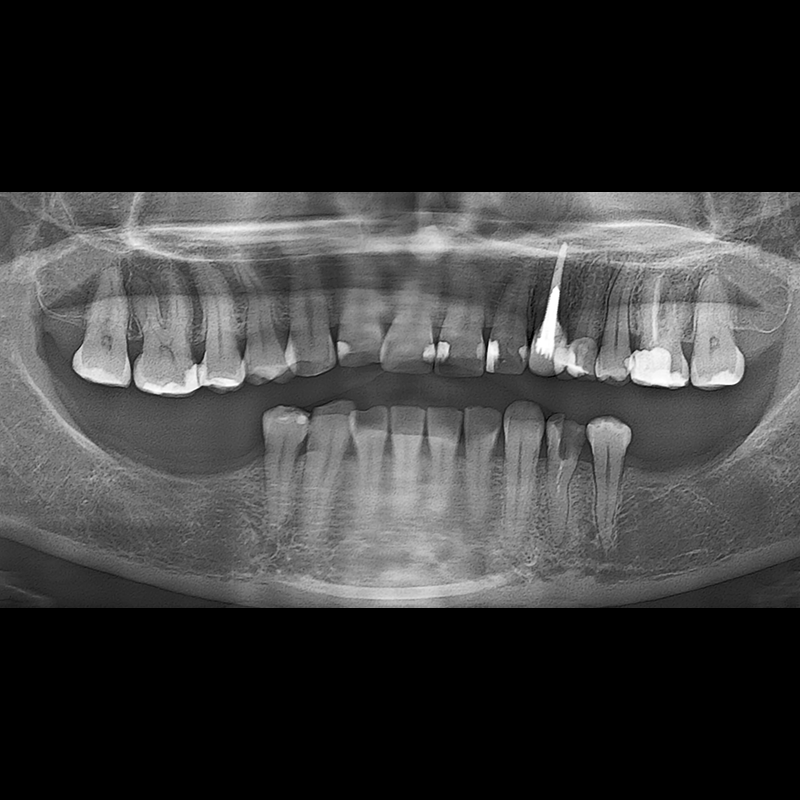

BEFORE AFTER

インプラント手術事例 2025.05.30

欠損した歯の部分と、生かしにくい歯の位置にインプラントを植立しました。